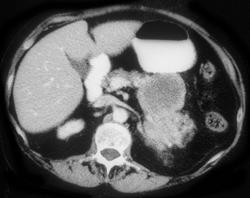

Normal Gastric Fold Enhancement. (note Ascites and Dilated Intrahepatic Ducts)